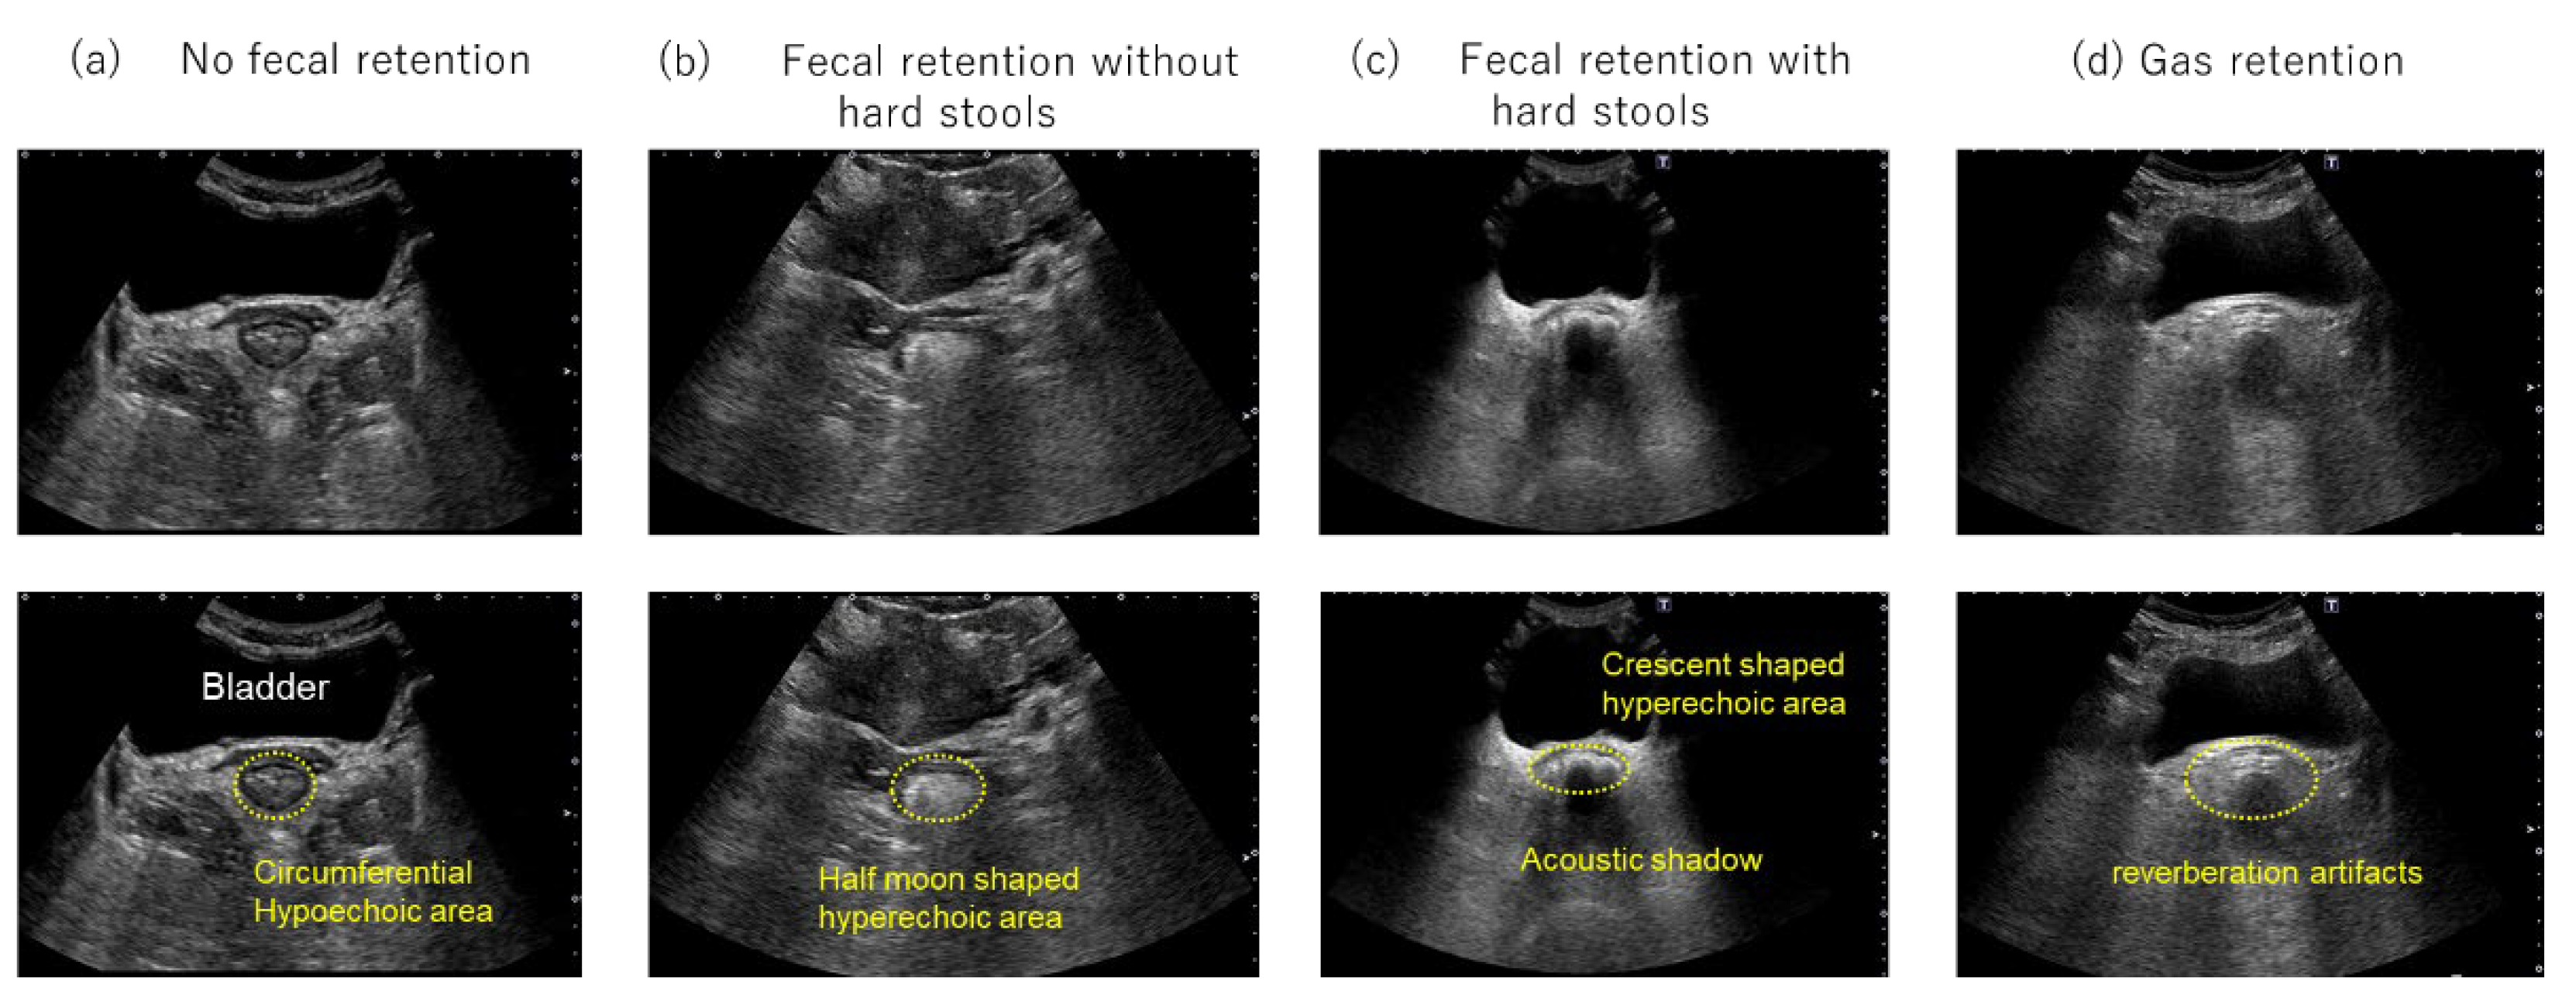

To classify rectal findings, the conventional three-category classification (no fecal retention, fecal retention without hard stools, and fecal retention with hard stools) was expanded by adding a fourth category, “gas retention.” The “gas retention” category was defined as the presence of multiple echoes with reverberation artifacts in the rectum on transabdominal US (Figure 1).

Figure 1. Transverse rectal ultrasound images. (a) No fecal retention, with no hyperechoic area observed. A circumferential hypoechoic area is observed in the lower part of the bladder. (b) Fecal retention without hard stools, revealing a half-moon-shaped hyperechoic area in the lower part of the bladder. (c) Fecal retention with hard stools, revealing a crescent-shaped hyperechoic area with an acoustic shadow in the lower part of the bladder. (d) Gas retention, multiple echoes with reverberation artifacts are observed in the lower part of the bladder.